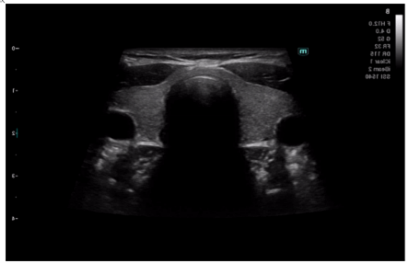

Ηχοβόλος κεφαλή τύπου Convex Array SC5-1N, τεχνολογίας μονού κρυστάλλου από 1,2 MHz έως 6,0 MHz με δυνατότητα επιλογής διαφορετικών συχνοτήτων στο B-Mode, Doppler, Έγχρωμο Doppler για απεικόνιση άνω κάτω κοιλίας, ουρολογίας, αγγείων, αορτή, γυναικολογίας μαιευτική κλπ.